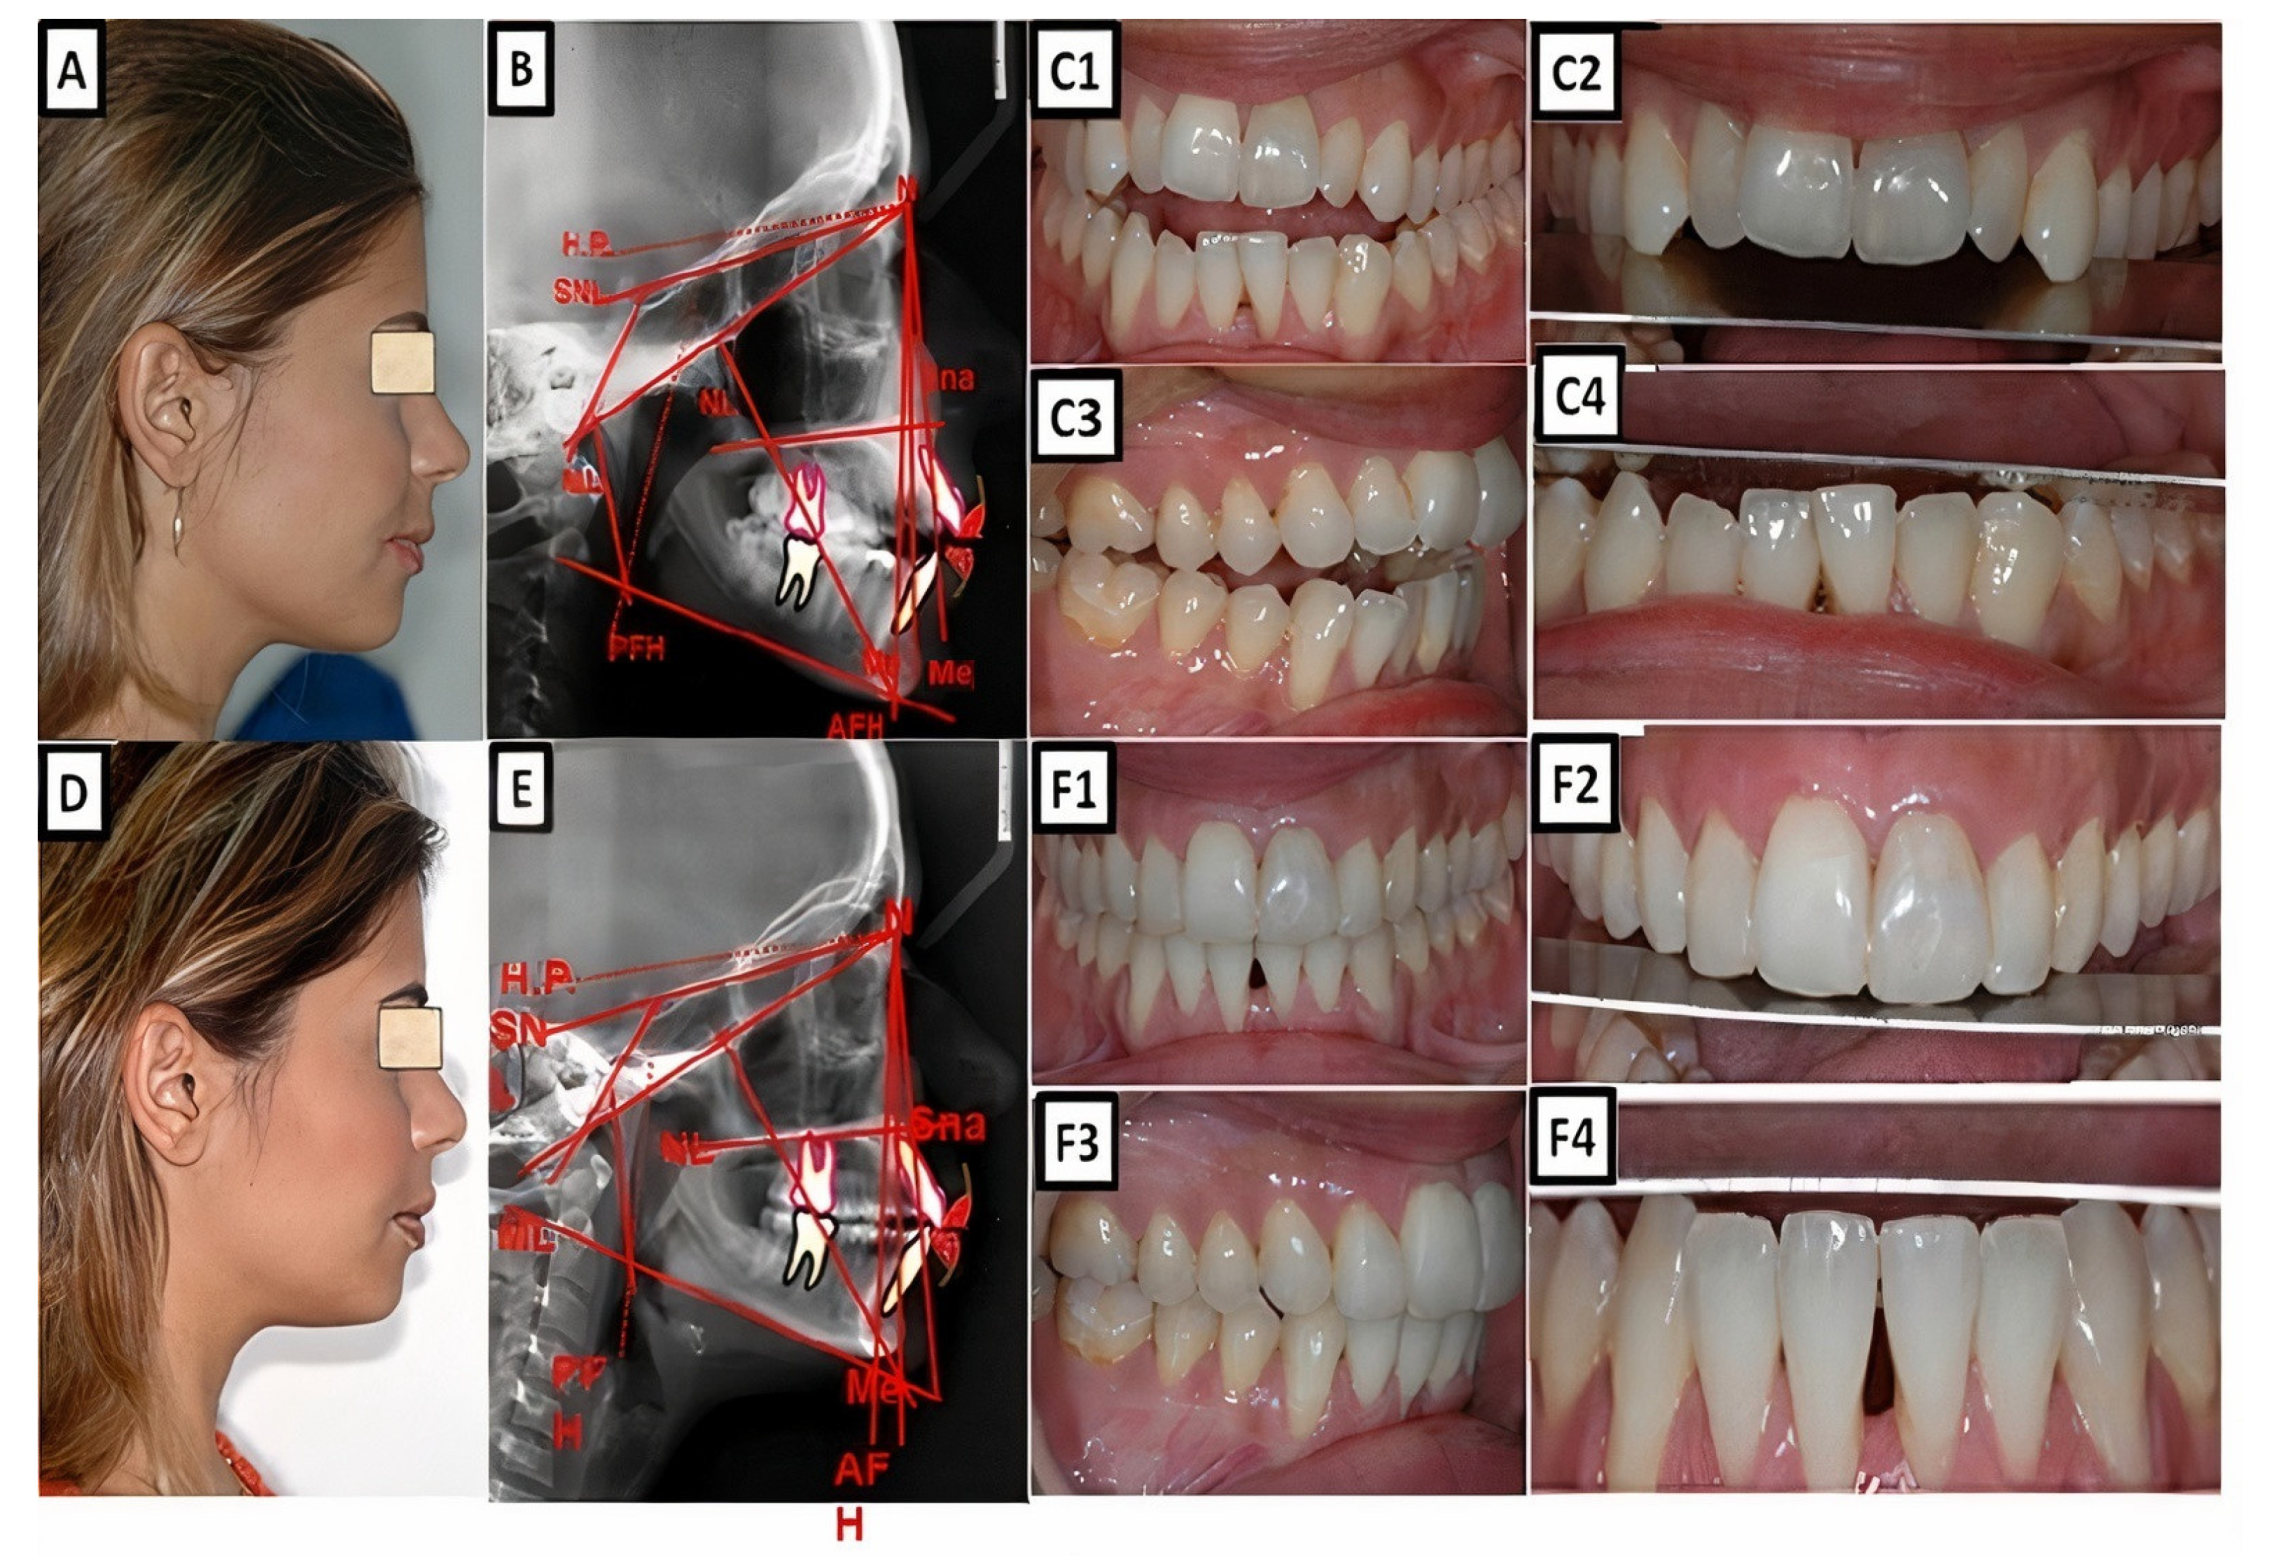

Figure 4.

Biometric photo and images of a patient with a Class I occlusion with a transverse problem in the maxilla on the right side (crossbite). The treatment was carried out by transverse up righting of the teeth. (A–C) are before treatment, and (D–F) are after treatment.

Figure 5.

Biometric photo and images of a patient with a Class I occlusion with a vertical problem (deep bite), crowding, and teeth malposition. (A–C) are before treatment, and (D–F) are after treatment.